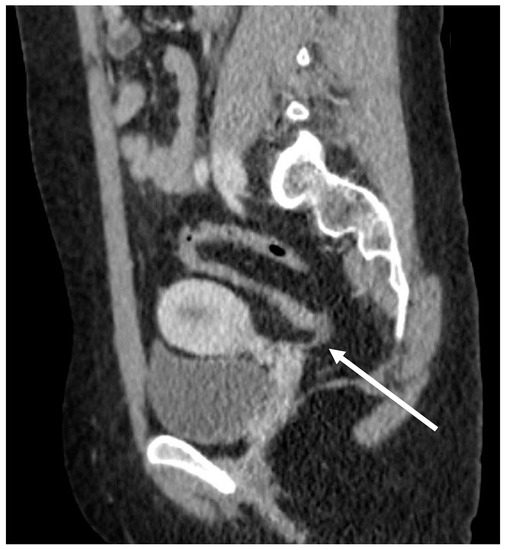

Small bowel stenosis after blunt abdominal trauma a case report

Small bowel stenosis after blunt abdominal trauma a case report What Is Bowel Narrowing If not treated, a blockage can lead to a dangerous rupture. It needs medical care right away, so see a doctor if you. A bowel obstruction is when one of your intestines becomes partly or completely blocked. A colon stricture, or intestinal stricture, is a narrowing of your large intestine (colon). A bowel obstruction is a partial or complete blockage. What Is Bowel Narrowing.